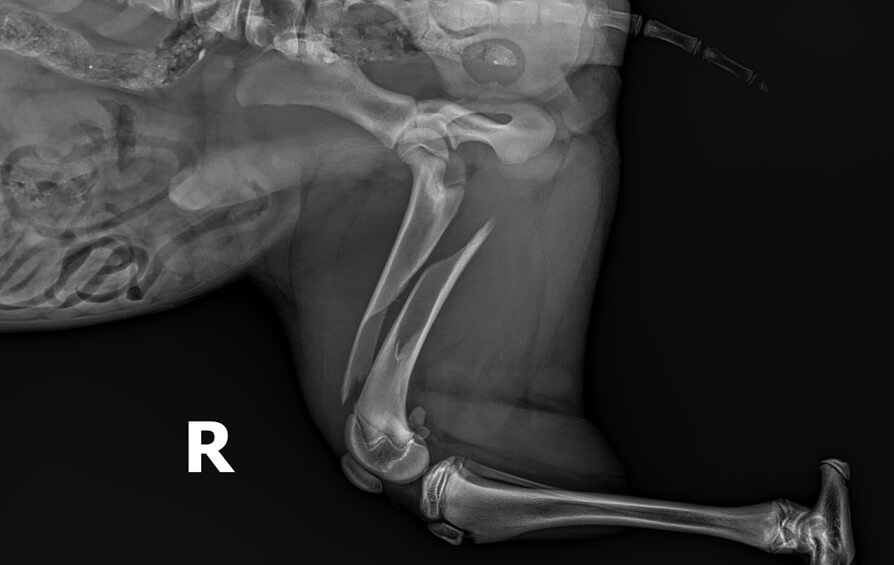

My dog had a massive wound that they first did the surgery on and then took care of our girls bandage changes everyday for two weeks straight. They saved my baby and I can't thank them enough. Pics of my baby for tax.

Ashley D.